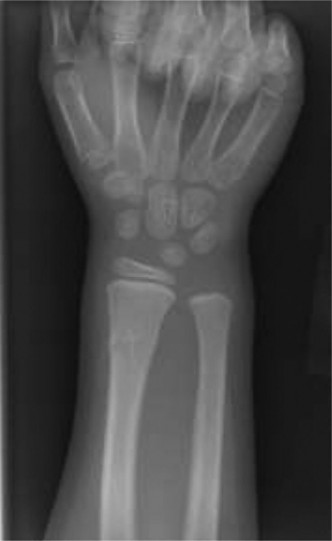

A 28-year-old, male, left hand-dominant, factory worker, and avid weight lifter presents to clinic complainin…